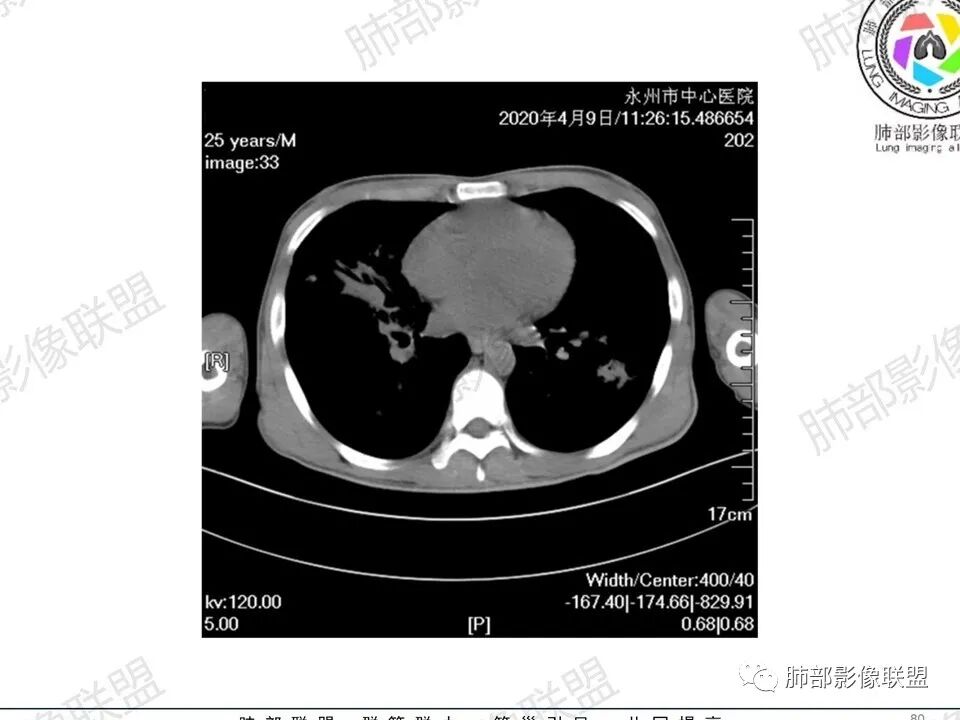

3、影像表现:双肺散在斑片影及结节影,部分结节内可见血管穿行,斑片影沿支气管血管束分布,近胸膜侧病变收缩不明显。部分中央淋巴间质增厚,小叶间隔增厚。病灶内支气管穿行,部分支气管略扩张。局部小结节呈串珠样改变。纵隔、肺门区、锁骨上及腋窝淋淋巴结肿大,部分有融合。心腔低密度。脾大。

2.双肺多发片影及结节影,边界可分辨,右肺中上叶较为密集,没有胸膜下分布优势。病灶实性密度为主,未见钙化及液化。

4.病灶区域穿行支气管显示良好,未见壁增厚及管腔狭窄。

5.双肺门及纵隔淋巴结显著增大,这改变相当显眼。这里强调“双肺门”及“多发”!

增大的淋巴结密度偏低且均匀。此外患者有体表淋巴结增大。

3.双肺多发结节影,没有明显的新旧不等,没有钙化,微小结节影密度偏低,边缘不够僵硬锐利;病灶区域穿行支气管显示良好,未见壁增厚及管腔狭窄,加之病灶如此广泛,病灶未见收缩、肺叶体积未见缩小,结核中毒症状不明显等等都不支持结核。

双肺门、纵隔及全身浅表淋巴结都增大,对于结核病而言还是少见一些。